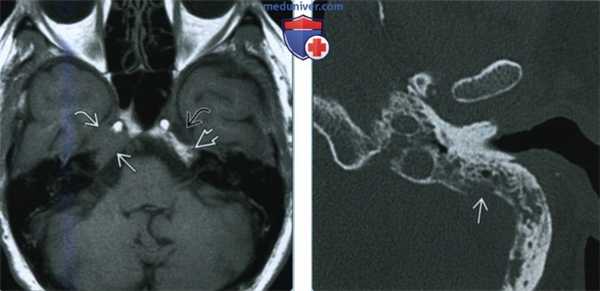

(Слева) При аксиальной МРТ Т1 ВИ у пациента с онемением правой половины лица определяется типичный метастаз в вершине пирамиды, замещающий жировой костный мозг, с распространением в полость Меккеля справа. Обратите внимание на нормальный сигнал в коаном мозге вершины пирамиды слева и ЦСЖ в полости Меккеля.

(Справа) При КТ определяется метааатическое поражение сосцевидного отростка с деструкцией кортикального слоя с внутренней аороны/сигмовидной пластинки с риском инвазии/тромбоза сигмовидного синуса. Из-за особенностей строения/пневматизации височной кости маленькие метастазы легко пропускаются.